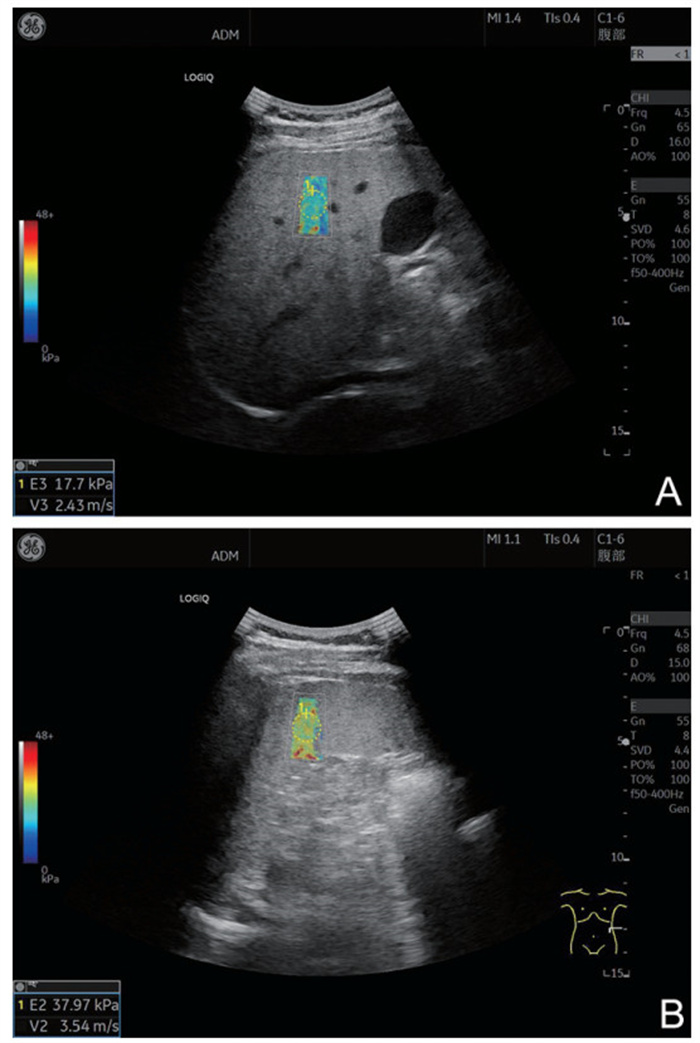

Prognostic effect of ultrasonic arterial flow parameters combined with serum ACA and AMH detection on fetal saving outcome of threatened abortion

GUAN Yanli, ZHANG Li, PEI Lijuan, ZHANG Mei

2025, 23(10): 1748-1752. doi: 10.16766/j.cnki.issn.1674-4152.004220

45 3

Abstract:

Objective  Threatened abortion (TA) may still lead to abortive failure after treatment. In this study, ultrasound arterial flow parameters in combination with serum anti-cardiolipin antibody (ACA) and anti-Mullerian hormone (AMH) were detected to explore the predictive effect of these indicators on abortive outcome, with a view to improving the success rate of TA.  Methods  The current study is based on a total of 135 TA patients admitted to Sanmenxia Hospital and Nanyang Central Hospital of the Yellow River from May 2021 to May 2023. According to the outcome of fetal protection, they were divided into a successful group (n=83) and a failed group (n=52). All patients had their ultrasonic arterial blood flow parameters and serum hormone levels checked. The influencing factors of fetal survival outcome were analyzed by means of a logistic regression model. The receiver operating characteristic (ROC) curve was utilized to analyze the predictive value of ultrasonic arterial flow parameters, serum ACA and AMH in the outcome of fetal protection.  Results  In contrast with the abortive group, the end-diastolic flow rate (D) and AMH levels in the abortive group were decreased, while the peak systolic flow rate (S)/D, pulse index (PI), resistance index (RI), ACA level and spontaneous abortion history, and the proportion of vaginal bleeding ≥50 mL were increased in the abortive group (P < 0.05). Logistic regression analysis showed that vaginal bleeding of ≥50 mL, elevated high levels of S/D, PI, RI and ACA were independent risk factors for fetal failure of TA (P < 0.05, OR>1), and high levels of AMH were protective factors (P < 0.05, OR < 1). The results of the ROC analysis demonstrated that the AUC of S/D, PI, RI, ACA and AMH were 0.724, 0.676, 0.752, 0.755, 0.692 and 0.880, respectively, and the combined prediction efficiency of the five factors was found to be superior to that of each individual test.  Conclusion  Abnormal ultrasonic arterial flow parameters in TA patients, among which high levels of S/D, PI, RI and ACA are risk factors for the failure of TA, and high levels of AMH are protective risk factors. The five combined tests have a high level of predictive capacity for the outcome of TA.